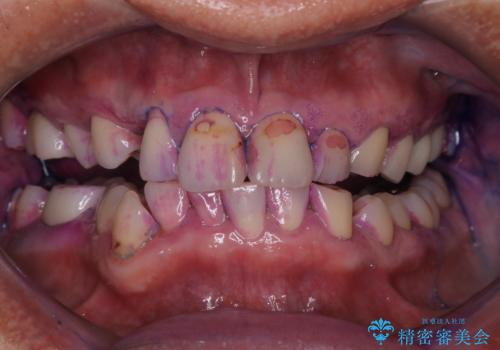

染め出しをして、磨き残しの確認・ブラッシング指導も行いました。

いくら綺麗なセラミックがセットされても、歯ブラシが適切にできないと汚れが付着します。治療が終わったら、改めて現状のお口の中に合わせたブラッシング指導を行い長期的に安定したお口の環境づくりにしていきます。